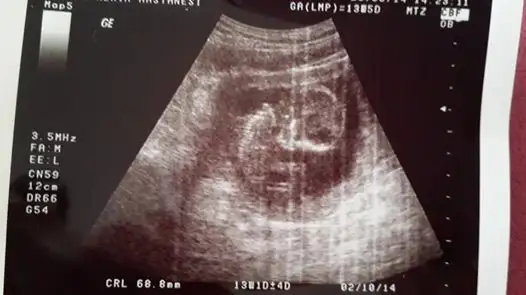

Eki Görüntüle 473829 bu bir erkek bebek genital nub cikintisi gayet yukarda

Eki Görüntüle 473831 simdi burada cikintilara bakin eger bel popo cizgisine paralel ise kiz

yok 30 derecelik bir aciyla yukari bakiyorsa erkek